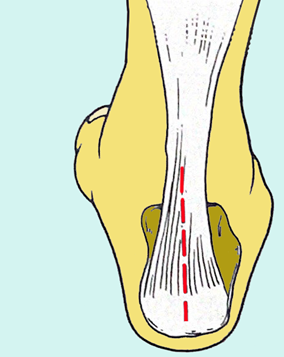

图1:跟腱的解剖示意图

跟腱是小腿三头肌,即腓肠肌和比目鱼肌的肌腹下端移行的腱性结构,止于跟骨结节,是人体最粗最大的肌腱之一,对机体行走、站立和维持平衡有着重要的意义。